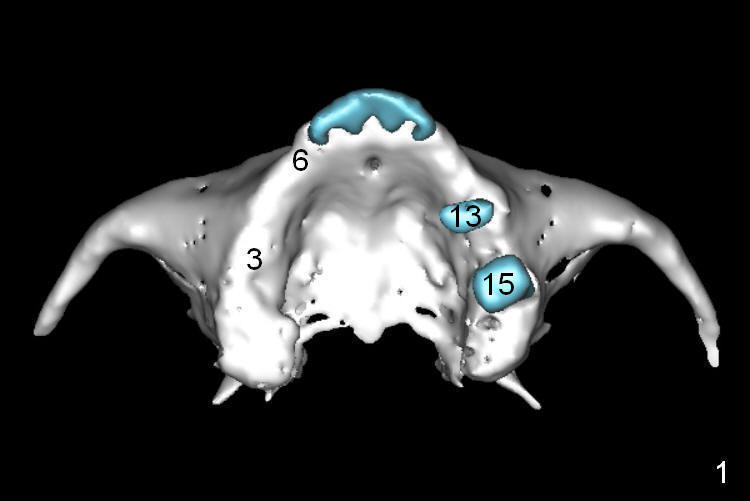

A 68-year-old lady has several missing teeth (Fig.1,2). She has agreed to have an implant at the site of #3 (Fig.3) to stabilize an upper removable partial denture (RPD). The latter will be more stable if an extra implant is placed at #6 (Fig.1,2,6). There is enough bone to place implants at #4,5 (Fig.4,5). Bone density at these sites is low. Osteotomy should be underprep with bone condensation. Edentulous space is high so long abutments are required (9 mm instead of 3 or 5 mm (regularly used)). Angled abutments should be prepared.